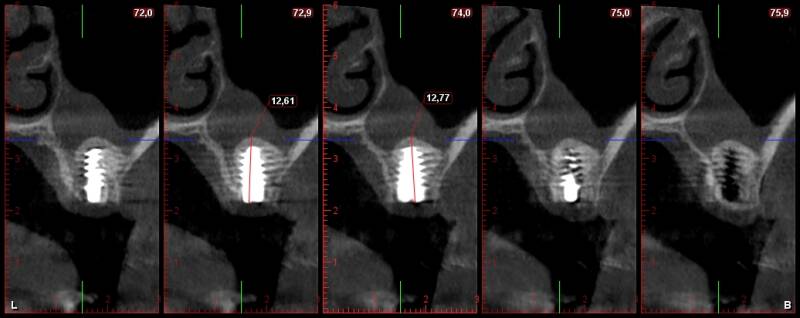

Elevacion de seno acceso lateral y crestal minimamente invasiva

Abordaremos soluciones prácticas y efectivas para posibles complicaciones intraoperatorias, tales como la perforación de la membrana de Schneider, la presencia de arterias, tabiques o cuerpos extraños. Te proporcionaremos las herramientas y el conocimiento necesario para resolver estas situaciones con confianza y precisión.

Nuestro objetivo es que, como resultado de esta residencia, puedas realizar todas las elevaciones de seno con éxito, permitiéndote colocar implantes de manera simultánea o diferida, según las necesidades de cada caso. Te proporcionaremos la capacitación y la experiencia práctica necesarias para lograr resultados predecibles y satisfactorios para tus pacientes.

ACCESO LATERAL

Miles de Elevaciones de Seno siempre con el mismo protocolo de exito.